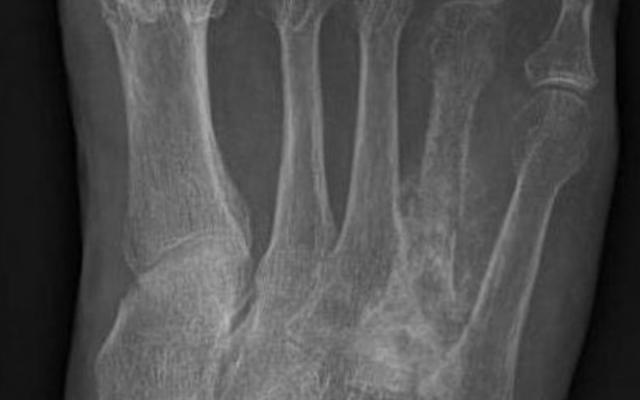

Dit artikel is alleen beschikbaar als PDF.Lees de PDF Artikelinformatie Online verschenen op 25 februari 1893 Citeer dit artikel als Ned Tijdschr Geneeskd. 1893;37:843-9 Heb je nog vragen na het lezen van dit artikel? Check onze AI-tool en verbaas je over de antwoorden. ASK NTVG Ook interessant Klinische les Niet-genezende tropenzweren Mededelingen Geoorloofde en niet-geoorloofde reclame voor geneesmiddelen Beeldquiz Niet-genezende fractuur in de voet Meer gerelateerd … Reacties Login om een reactie te plaatsen